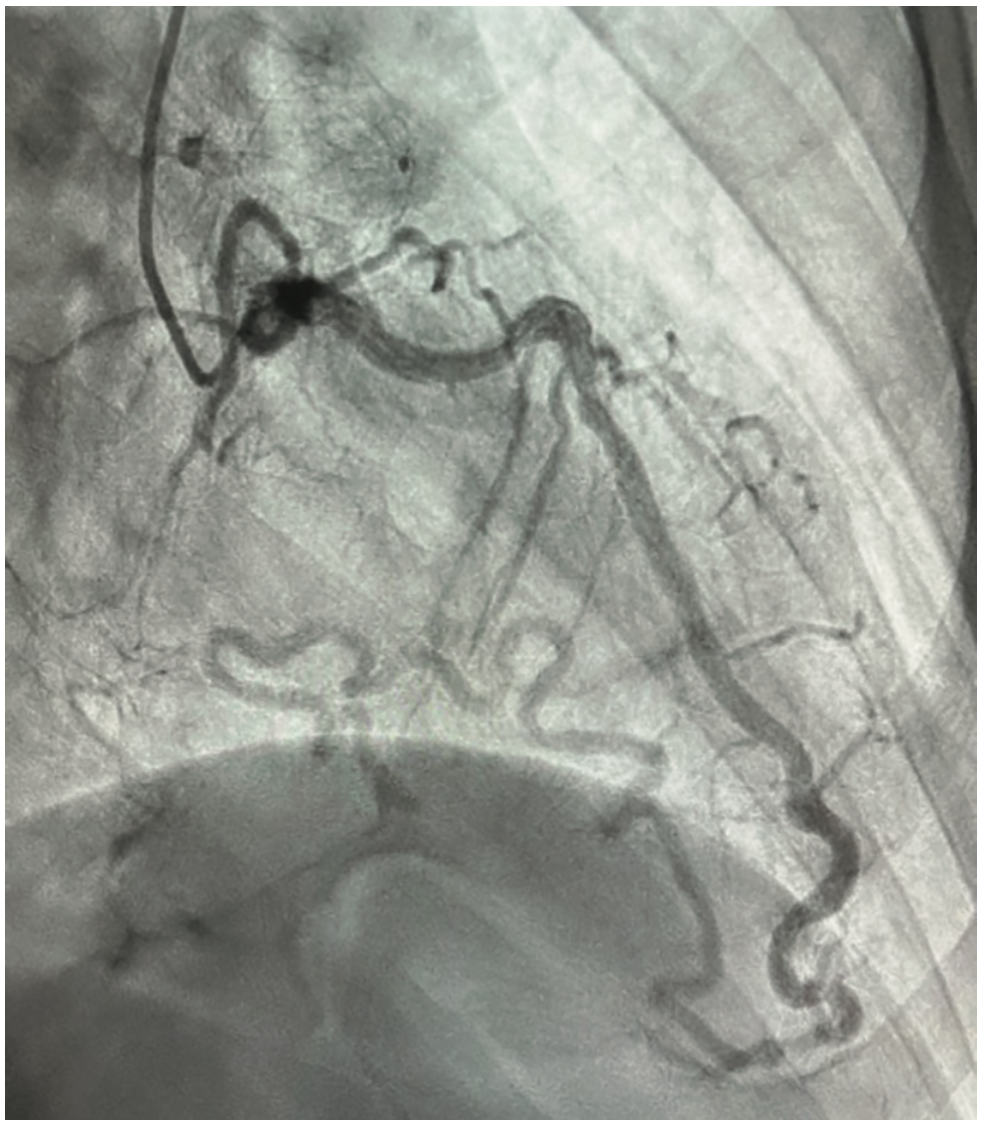

The patient is a 76-year-old male with a past medical history of hypertension, peripheral arterial disease (PAD), myocardial infarction (MI) two years ago, and hyperlipidemia, presenting with dyspnea on exertion. He was suspected of having coronary artery disease (CAD) after an abnormal stress test, and subsequently underwent a left and right coronary artery catheterization through the right radial artery. The patient was given 2 mg of midazolam and 200 mcg of fentanyl intravenously for a total sedation time of less than a minute. Access was achieved using a modified Seldinger technique with a 6 French catheter placed in the right radial artery. A 5 French catheter was then placed to engage the left coronary artery. Angiography showed a patent left main coronary artery and an 80% stenosis in the mid LAD. There was a small, patent, non-dominant LCX, and a dominant RCA with a chronic total occlusion and evidence of left and right collaterals. The ejection fraction was 60% and left ventricular end diastolic pressure was 14 mmHg. The LAD was noted to have an unusual course across the anterior heart. The extension of the LAD wrapped around the apex and supplied a large portion of the posterior heart, providing left and right collaterals. After further consideration, this vessel was identified as the left obtuse marginal artery coming off the LAD rather than the left circumflex artery, suggesting an anomalous coronary artery (Figures 1-3). Due to the patient’s multivessel CAD, cardiothoracic surgery was consulted for coronary artery bypass graft (CABG) evaluation. The patient underwent off-pump CABG x2 with left internal mammary artery to the LAD and a reverse saphenous vein bypass graft from the aorta to the distal RCA. He tolerated the procedure well and was subsequently taken to the cardiovascular intensive care unit in stable condition.